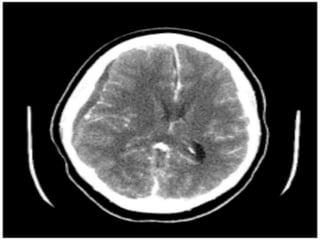

Grey and white matter differentiation

• Normally Grey matter is outer denser

structure and white matter in inner

hypodenser.

• Grey matter contains neurons cell bodies

while white matter contain axons with rich

fatty myelin sheath making it hypodense.

• This differentiation is loss in case of cerebral

odema.

Normal Grey white matter